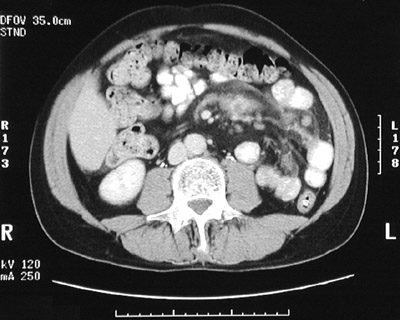

There is a mass composed of enlarged lymph nodes seen in this abdominal CT scan. In the view below, there is a central area of decreased intensity in the mass that corresponds with central caseous necrosis as a result of mycobacterial infection.